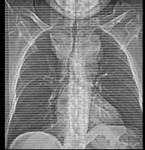

男,41岁,体检X线提示纵隔增宽,CT检查如图,请选出最可能的诊断 ( )A.淋巴瘤B.纵隔畸胎瘤C.胸腺瘤D.间皮囊肿E.胸内甲状腺肿

问题 男,41岁,体检X线提示纵隔增宽,CT检查如图,请选出最可能的诊断 ( )

选项 A.淋巴瘤 B.纵隔畸胎瘤 C.胸腺瘤 D.间皮囊肿 E.胸内甲状腺肿

答案 E